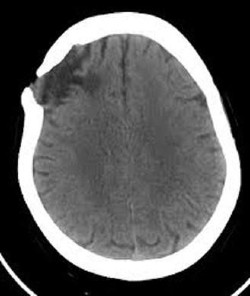

Hématome épidural

Il présente deux faces concaves opposées; il se trouve entre la voûte crânienne et la dure-mère (l’une des membranes enveloppant le cerveau). Les symptômes de ce type d’hématome sont des intervalles de lucidité et de perte de conscience.

Hématome sous-dural

Il présente une forme de croissant et se localise entre deux des trois membranes du cerveau. Des maux de tête et des signes de confusion peuvent être perçus chez les patients ayant ce type d’hématome.

Hématome extra-crânien

Il est de moindre gravité, car il se loge entre les différentes couches situées entre la voûte crânienne et la peau.